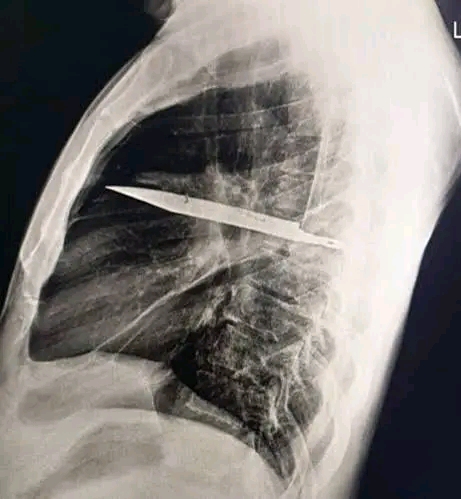

The X-ray revealed a “retained metallic object in the mid-thorax” that had entered through his right shoulder blade. Miraculously, the blade had somehow managed to avoid all his major organs. What doctors found even more bizarre was that the knife had caused the man no discomfort for so long. The pus discharge that led to the discovery was a result of dead tissue building up around the foreign object.